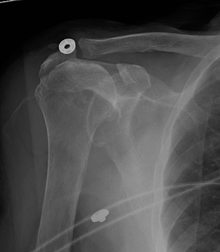

Diagnostic modalities, dependent on circumstances, include X-ray, MRI, MR arthrography, double-contrast arthrography, and ultrasound. Although MR arthrography is currently considered the gold standard, ultrasound may be most cost-effective.[16] Usually, a tear will be undetected by X-ray, although bone spurs, which can impinge upon the rotator cuff tendons, may be visible.[17] Such spurs suggest chronic severe rotator cuff disease. Double-contrast arthrography involves injecting contrast dye into the shoulder joint to detect leakage out of the injured rotator cuff[18] and its value is influenced by the experience of the operator. The most common diagnostic tool is magnetic resonance imaging (MRI), which can sometimes indicate the size of the tear, as well as its location within the tendon. Furthermore, MRI enables the detection or exclusion of complete rotator cuff tears with reasonable accuracy and is also suitable to diagnose other pathologies of the shoulder joint.[19]

The logical use of diagnostic tests is an important component of effective clinical practice.[20] X-rays cannot directly reveal tears of the rotator cuff, a 'soft tissue', and consequently, normal X-rays cannot exclude a damaged cuff. However, indirect evidence of pathology may be seen in instances where one or more of the tendons have undergone degenerative calcification (calcific tendinitis). Also, large tears of the rotator cuff may allow the humeral head to migrate upwards (high-riding humeral head) which may be visible on X-ray. Prolonged contact between a high-riding humeral head and the acromion above it, may lead to X-rays findings of wear on the humeral head and acromion and secondary degenerative arthritis of the glenohumeral joint (the ball and socket joint of the shoulder), called cuff arthropathy, may follow.[21] Incidental X-ray findings of bone spurs at the adjacent acromioclavicular joint may show a bone spur growing from the outer edge of the clavicle downwards towards the rotator cuff. Spurs may also be seen on the underside of the acromion, once thought to cause direct fraying of the rotator cuff from contact friction, a concept currently regarded as controversial.